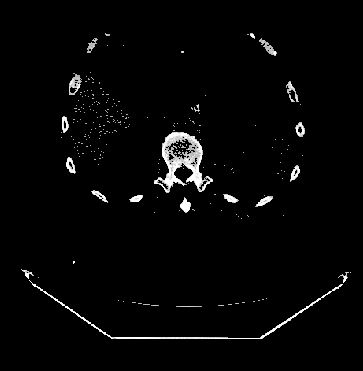

同时,DcmViewer支持移动端,当屏幕不足够大时,只显示最基本的视图布局切换和影像图片导航功能(样例数据将不支持冠状面和矢状面)。

小屏幕移动端: